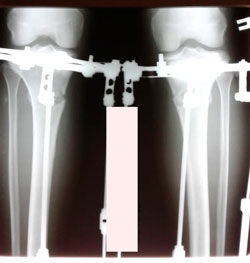

Исходник 36 лет.

Дата операции - 08.10.2020

image-07-10-20-06-46-4.jpg

image-07-10-20-06-46.jpg